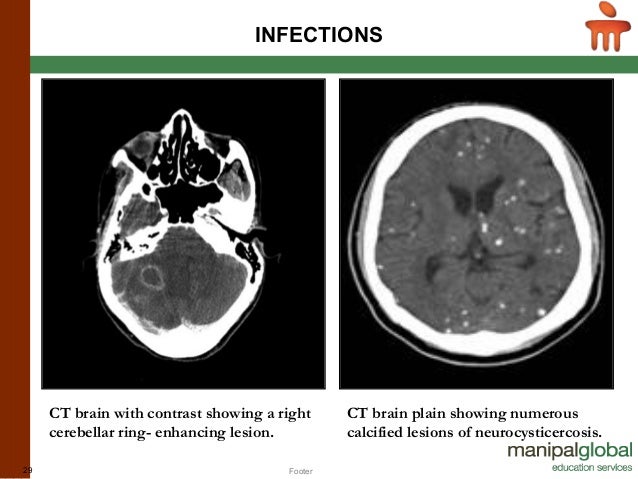

Image source: https://image.slidesharecdn.com/ctpet-150513094344-lva1-app6892/95/basics-in-neuroimaging-ct-mri-and-pet-29-638.jpg?cb=1434126464